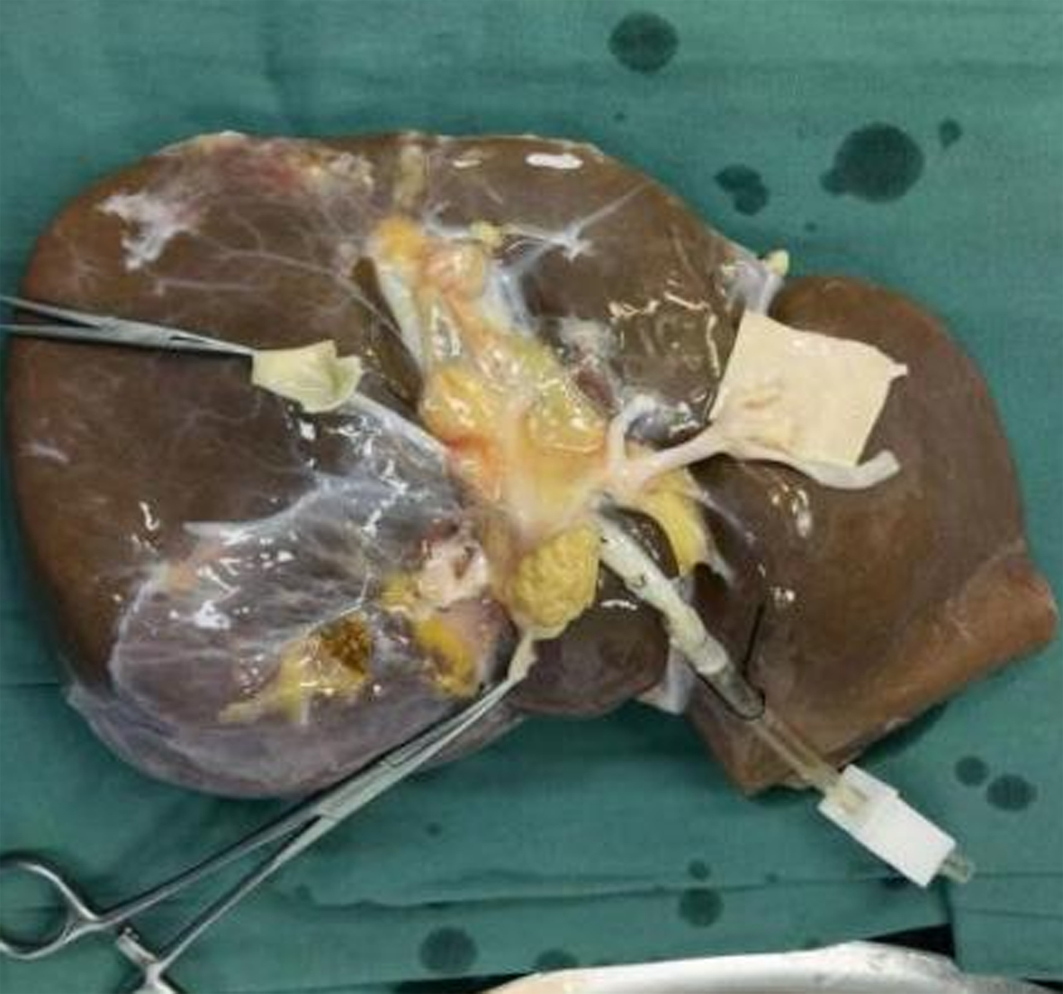

Autoimmune pancreatitis involving left iliac paravascular tissue: A case report

Xin YANG, Lamei LI, Qi ZHU, Xinle YANG, Xinrui WANG, Yanjun CAI, Wanyu LI

2022, 38(12): 2824-2826. DOI: 10.3969/j.issn.1001-5256.2022.12.026

Abstract(1790) HTML (1077) PDF (2345KB)(83)

Abstract: